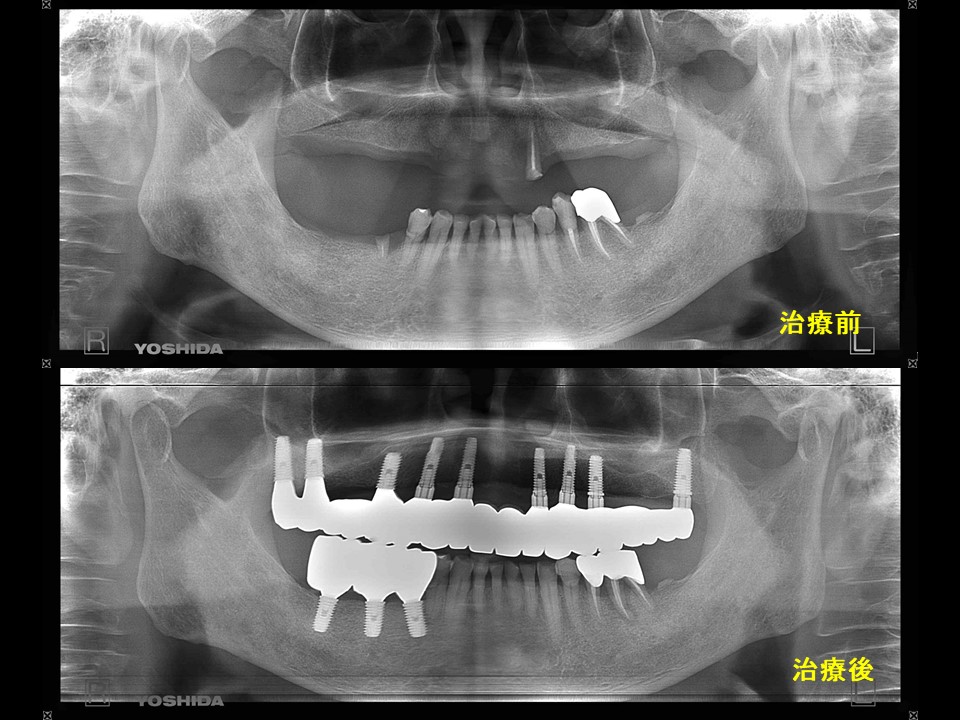

症例16